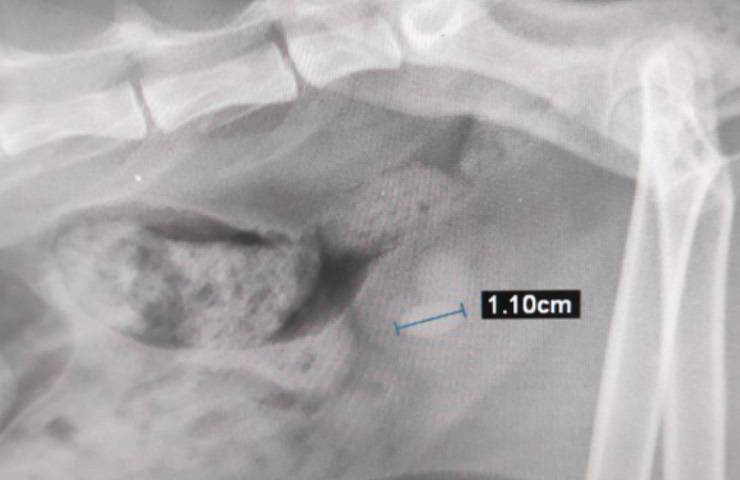

Quando – alcune settimane fa – Giuliano è stato visitato, si è scoperto che il felino soffriva di calcoli e che questi ultimi erano in procinto di compromettere il suo organismo lasciando che le sue condizioni di salute potessero degenerare da un momento all’altro. Fortunatamente, grazie alla solidarietà della comunità, tutto ciò è stato esemplarmente evitato. “Ora” infatti Giuliano, informano i volontari in un ultimo post condiviso il 6 dicembre scorso, “è stato operato e sta bene“.

Le immagini della radiografia e del primo piano di Giuliano, dopo l’operazione chirurgica, sono state pubblicate su Facebook dalla pagina ufficiale di “Pet Food by Falko Pesca Sport”, la quale ha preso molto a cuore la commovente storia del sensibile felino in difficoltà.